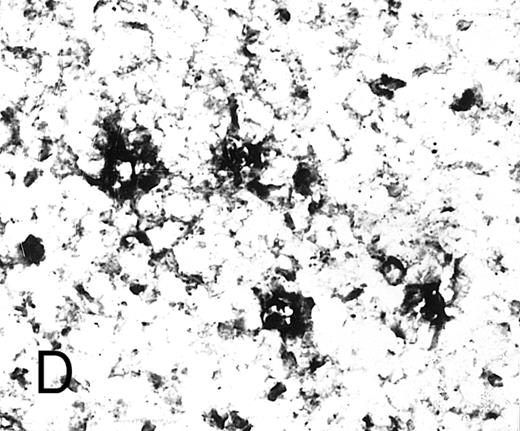

Expression of GM-CSF and GM-CSFRα in tonsillar lymphoid follicle. (A) Immunostain of GM-CSF. Some positive lymphocytes are scattered in the germinal center, but the distinct reticular pattern was not found. Counterstained with methyl green. Original magnification × 90. (B) Immunostain of GM-CSFRα. The distinct lacy pattern is found in the light zone and often in the outer and mantle zones. MZ, mantle zone; ALZ, apical light zone. Counterstained with methyl green. Original magnification × 240. (C) Immunoelectron micrograph of GM-CSFRα on FDC. Note a positive reaction on the surface of binucleated FDC embracing lymphocyte (L) of FDC. Bar = 1 nm. Original magnification × 5,700. (D) In situ hybridization of GM-CSFRα oligonucleotide. Dendritic-shaped cells are heavily labeled. Uncounterstained. Original magnification × 386.

Some GC lymphocytes were positive for GM-CSF (Fig 3A). No distinct positive reticular pattern was found in GC. On the other hand, the ALZ was heavily labeled in the reticular pattern and rarely in the dotted pattern for GM-CSFRα (Fig 3B). The BLZ was also weakly positive, and the OZ and MZ were often reacted. Immunoelectron microscopy confirmed that FDCs were positive for GM-CSFRα on their surface (Fig 3C). In situ hybridization also showed the expression of mRNA of GM-CSFRα in the cytoplasm of dendritic-shaped cells in the LZ and often in the OZ and MZ (Table 5 and Fig 3D). A few of the lymphocytes were positive for GM-CSFRα in the LZ. RT-PCR of samples from complete tonsillar tissue as well as GC and EGC showed a single-positive band (682 bp; Table 6 and Fig 2B).